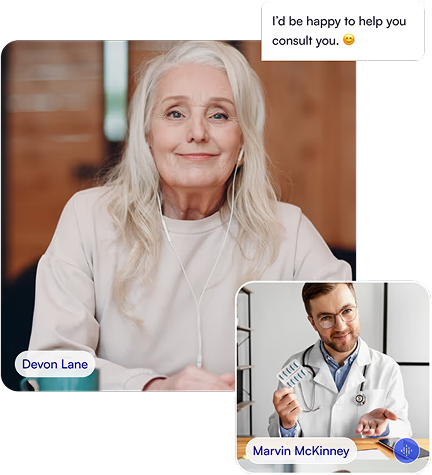

Patient reach us

Diagnosis & Treatment